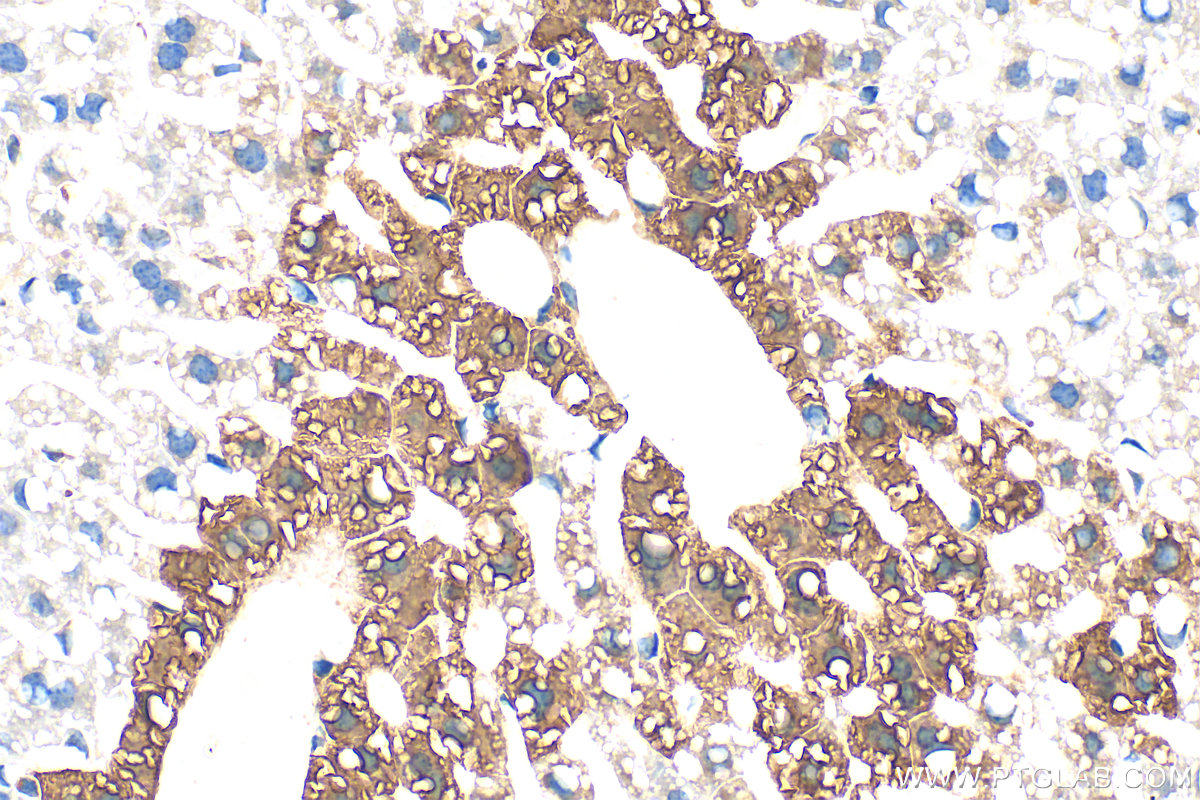

| Positive IHC detected in | mouse liver tissue Note: suggested antigen retrieval with TE buffer pH 9.0; (*) Alternatively, antigen retrieval may be performed with citrate buffer pH 6.0 |

| Immunohistochemistry (IHC) | IHC : 1:2000-1:8000 |